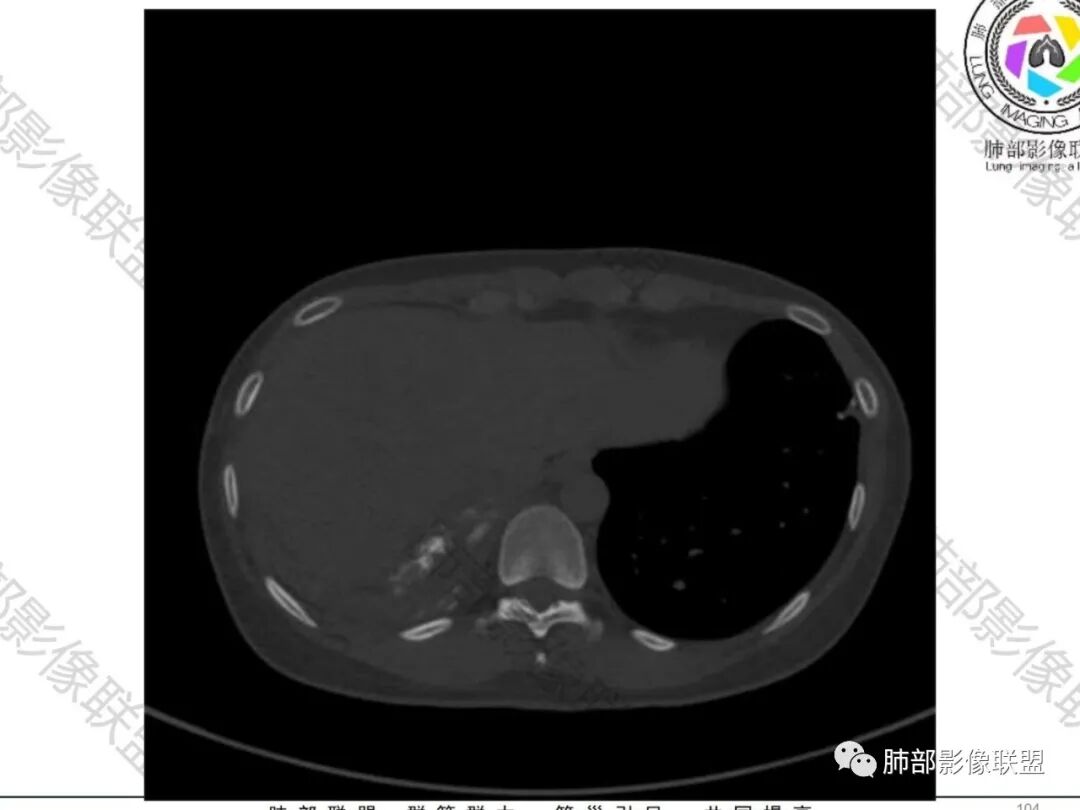

一切∮随缘:双侧胸廓塌陷,以右侧为主,右侧肋间隙狭窄,双肺上叶及右肺下叶胸膜下多发不规则肿块,密度不均匀,内部可见条片状,不规则钙化影,部分钙化不密实,双肺多发纤维索条影,似陈旧性病灶,双侧胸水,临床年轻女性,无感染症状,考虑考虑结核淀粉样变,转移性钙化,弥漫性肺骨化病。

尘缘:青年女性,痰中带血,胸痛2月,无发热盗汗,实验室检查,有贫血,总蛋白降低,血沉情况未知,肿标基本正常。影像表现:双上肺小叶间隔增厚,双侧胸膜广泛不规则增厚,胸膜下多发肿块伴不规则钙化,右侧肋骨破坏。纵隔淋巴结肿大不明显,双肺门淋巴结肿大,部分融合,分析思路:一、感染性病变,1、结核,青年女性,胸膜增厚,多发肿块伴钙化,有咳嗽胸痛,痰中带血,要考虑,但无结核中毒症状,病史仅两月却钙化太明显,肺内没有明显树芽征,存疑,2、其他感染,无炎性指标支持,白细胞不高,可能性小。二、非感染性病变,1、尘肺,胸膜增厚,钙化,胸膜下钙化性肿块,要考虑,但肺内无粉尘结节,无职业史,可能小。2、转移性钙化,无肾脏病史,无血清钙磷代谢异常指标支持,肺内间质无钙沉积改变,基本排除。三、肿瘤性病变,1、肺癌伴转移,双上肺有小叶间隔增厚,双肺门有淋巴结肿大,要考虑,但青年女性,病史两月,钙化太多太广泛,肿标基本正常,可能性小。2、骨肉瘤转移。15-30岁青年人,是骨肉瘤高发年龄,肺内多发成骨样钙化转移灶,双上肺小叶间隔增厚符合癌淋样表现,右侧肋骨破坏,要高度怀疑,需要详细询问病史及手术史。3、软骨来源肿瘤伴肺内转移,右侧肋骨虽有破坏,但无明显软骨样破坏及钙化。可能小。4、其他肿瘤伴转移,青年女性,其他恶性肿瘤能广泛发生钙化性转移的可能性小。综上所述:骨肉瘤伴右侧肋骨及胸膜转移,胸膜下转移,肺内癌淋可能最大,结核不完全除外,下一步需要,仔细询问病史,如果有骨肉瘤史,则基本确诊,如果没有,需要进一步问询呼吸系统症状,病程,以前的影像对照,了解肾脏情况,查血清钙磷指标。

骨质破坏,但是密度增高

南边:那就是说这个肋骨是自身的病变,有成骨性骨质破坏

肋骨伴随有溶骨性/成骨性骨质破坏,常规还是要警惕恶性